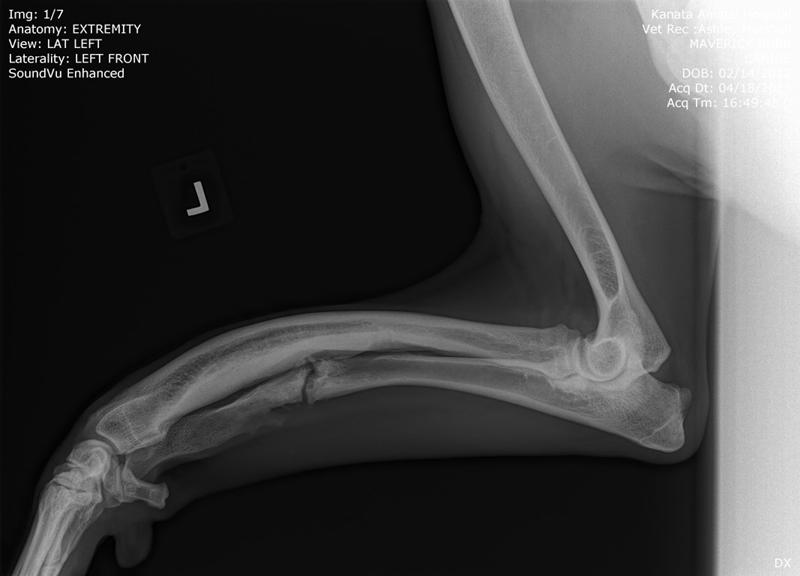

His surgery to remove the implant on his left front leg after a sudden rejection/infection with the plate screws was on September 24th. This is his fourth leg surgery. He had two surgeries on his front legs which were deformed when he first arrived to BHRR and then now he has had to have two more surgeries due to reacting to the Implants.

BHRR’s Mavie, for those who are not familiar with his journey has had two surgeries on his front legs, ended up reacting to the fixator on the left front leg, then last November rejected the implant in the right front leg and now, is having symptoms very similar on the left front leg.

Sadly, BHRR’s Maverick began to suddenly favour the left front leg that has the remaining implant in it last night. As of this AM, he was not weight bearing and though he did not have a fever, it was a bit warm and swollen and he was brought into KAH.

As many are aware, in November of 2014, BHRR’s Maverick, had a violent aggressive reaction to the implant in his right front leg and had to spend several months on strong antibiotics, had to have an emergency surgery to remove the plate/screws and was treated for a terrible abscess from reacting to the implant. His ortho specialist even cultured the implant to see what may be brewing on it…..

How it started with his right leg is how his left leg is now ‘appearing’ to be.

Needless to say, I was and am worried and a thorough exam was done, x-rays under sedation – HENCE, this lovely snoring sleepy photo of BHRR’s Mavie on the x-ray table!

At this time the integrity of the plate and leg look good, he is stil not running a fever and he will be on Tramadol and Deramaxx for pain and inflammation.